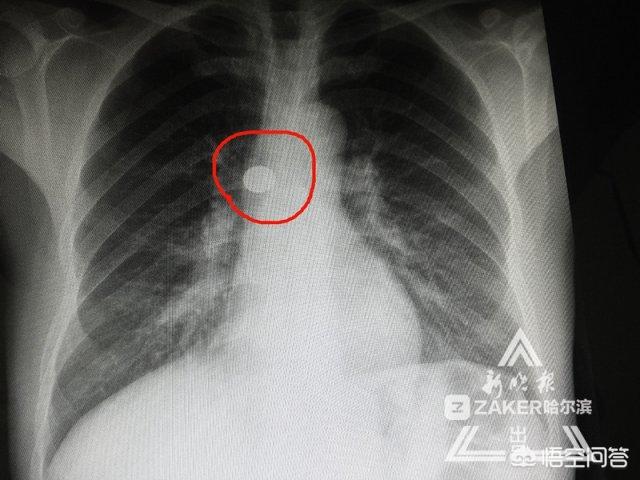

陈先生吓了一跳连夜赶到哈医大二院,经过X光胸透,确定右主支气管有圆形金属异物。由于右下肺出现感染,气管有脓性分泌物,必须尽早取出金属物,避免感染加重!